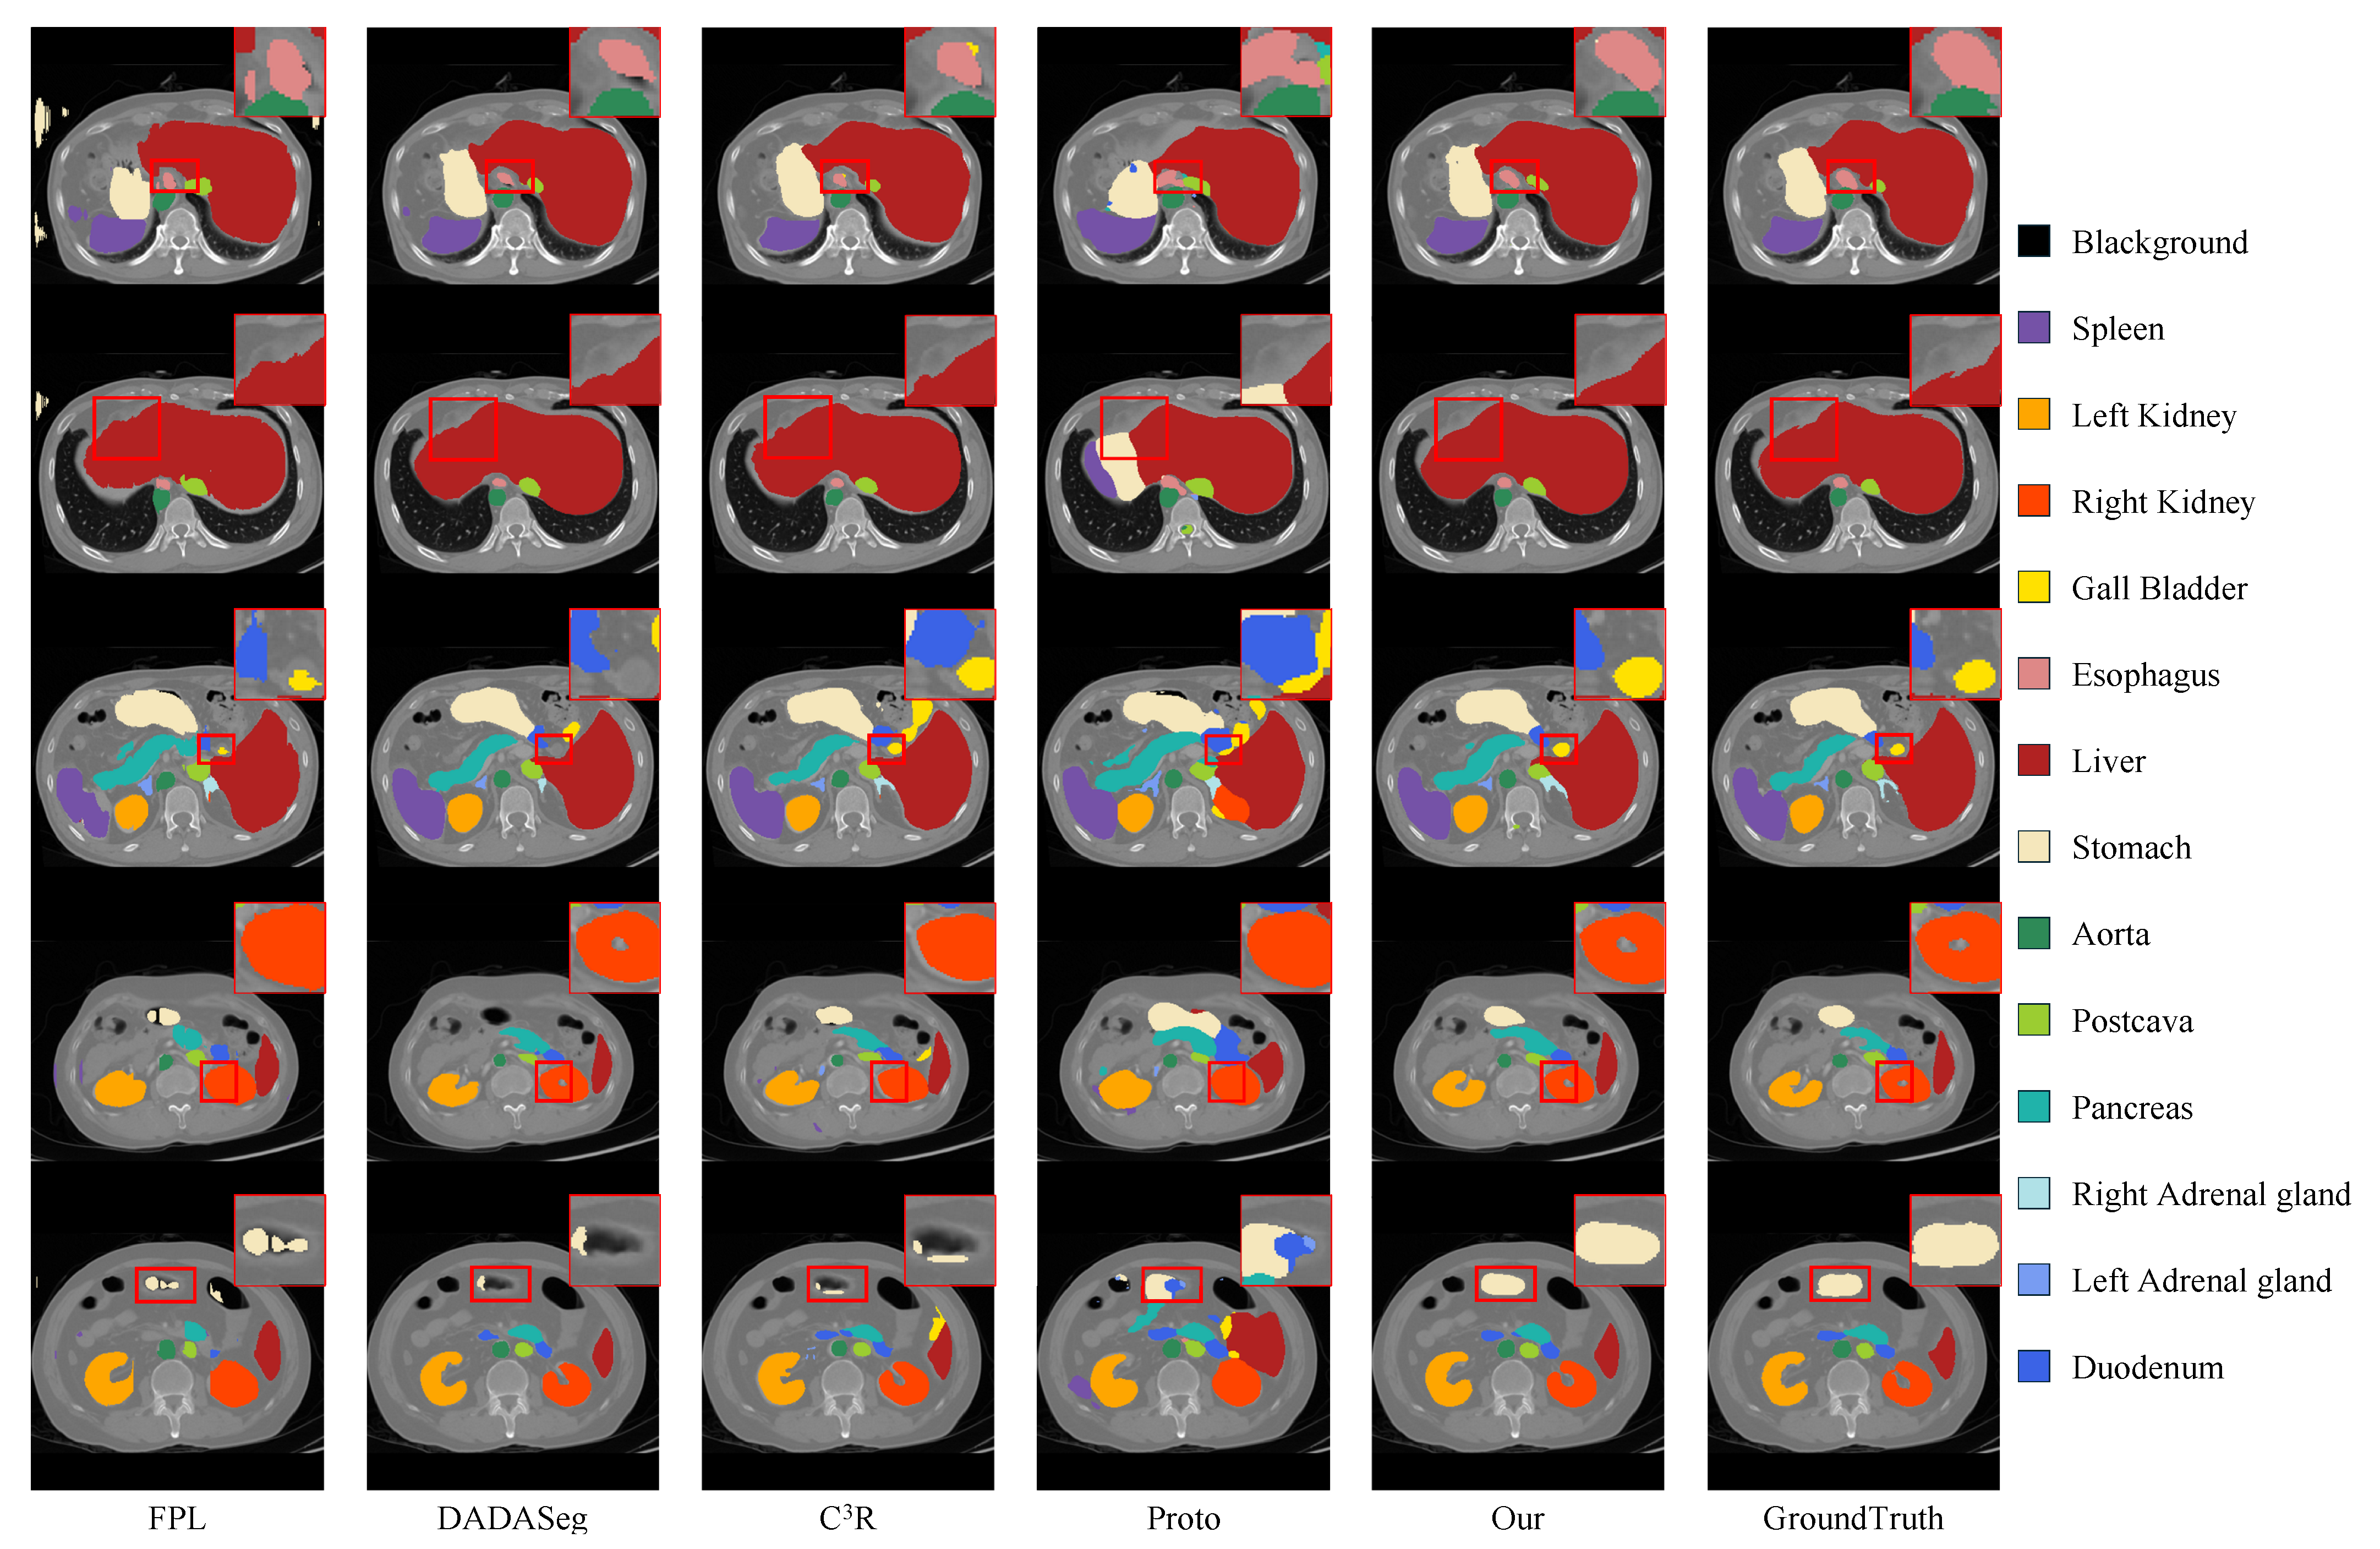

4.2. Quantitative and Qualitative Results

| Dice (%) ↑ | FPL [18] | DADAseg [22] | C3R [24] | AOS [25] | Proto [26] | UPL [11] | Ours |

|---|---|---|---|---|---|---|---|

| Spleen | 61.09 ± 25.16 ** | 85.30 ± 11.87 | 70.22 ± 18.72 ** | 2.46 ± 1.06 ** | 60.55 ± 17.82 ** | 13.18 ± 6.44 ** | 86.86 ± 10.62 |

| Right kidney | 74.59 ± 18.45 ** | 72.15 ± 13.09 ** | 77.71 ± 13.17 | 1.40 ± 0.39 ** | 56.25 ± 25.67 ** | - | 81.85 ± 22.41 |

| Left kidney | 72.72 ± 24.32 ** | 82.82 ± 16.18 | 75.84 ± 12.84 | 1.04 ± 0.33 ** | 59.35 ± 23.36 ** | 0.02 ± 0.10 ** | 79.22 ± 22.47 |

| Gall bladder | 35.44 ± 28.87 ** | 31.65 ± 18.63 ** | 29.81 ± 23.18 ** | 0.34 ± 0.31 ** | 15.53 ± 14.29 ** | - | 50.25 ± 31.20 |

| Esophagus | 25.74 ± 21.23 ** | 45.20 ± 24.27 ** | 49.02 ± 21.66 ** | 0.13 ± 0.09 ** | 26.94 ± 17.40 ** | - | 57.70 ± 24.36 |

| Liver | 80.89 ± 9.80 ** | 92.44 ± 5.57 | 82.58 ± 10.58 ** | 6.21 ± 0.64 ** | 77.00 ± 10.82 ** | 42.23 ± 9.70 ** | 88.58 ± 8.98 |

| Stomach | 34.82 ± 23.93 ** | 53.98 ± 28.90 ** | 58.20 ± 21.35 | 2.64 ± 1.18 ** | 39.63 ± 15.97 ** | 6.86 ± 6.11 ** | 58.96 ± 22.47 |

| Aorta | 62.84 ± 22.91 ** | 86.45 ± 8.92 | 78.12 ± 8.26 ** | 1.12 ± 0.45 ** | 68.76 ± 22.85 ** | 8.63 ± 4.09 ** | 82.59 ± 14.18 |

| Postcava | 56.03 ± 14.94 ** | 75.12 ± 11.60 | 64.46 ± 12.21 | 1.00 ± 0.28 ** | 46.40 ± 17.26 ** | - | 63.28 ± 16.34 |

| Pancreas | 45.20 ± 21.44 ** | 59.26 ± 18.73 | 57.50 ± 15.67 | 0.80 ± 0.23 ** | 30.94 ± 19.05 ** | - | 50.17 ± 19.20 |

| Right adrenal gland | 36.97 ± 18.67 | 29.41 ± 15.86 ** | 31.67 ± 10.35 ** | 0.04 ± 0.02 ** | 17.02 ± 14.99 ** | - | 40.35 ± 21.08 |

| Left adrenal gland | 33.24 ± 22.10 | 19.94 ± 17.85 ** | 17.11 ± 12.59 ** | 0.05 ± 0.02 ** | 16.55 ± 13.79 ** | - | 34.13 ± 24.89 |

| Duodenum | 26.89 ± 16.14 ** | 44.31 ± 19.69 | 40.60 ± 14.53 ** | 0.60 ± 0.23 ** | 17.92 ± 11.81 ** | - | 45.17 ± 18.97 |

| Avg | 49.73 ± 13.34 ** | 59.85 ± 8.91 ** | 56.37 ± 9.06 ** | 1.37 ± 0.19 ** | 40.99 ± 12.61 ** | 5.46 ± 1.14 ** | 63.01 ± 12.61 |